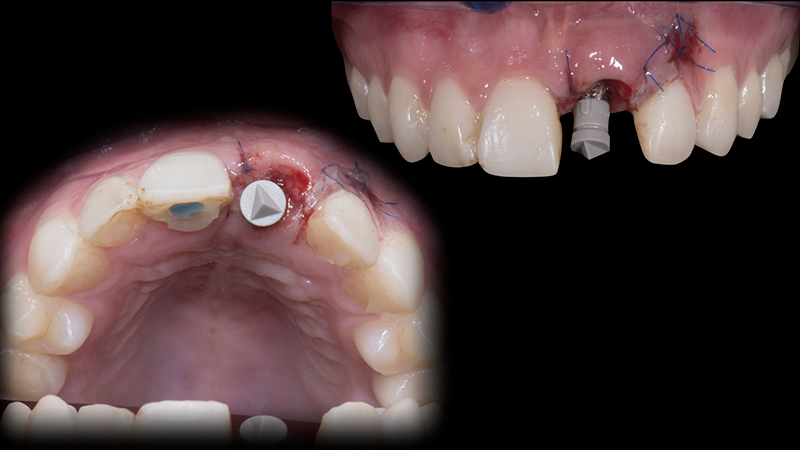

L'obiettivo è inserire un impianto nella cresta ossea rigenerata e ripristinare il volume del tessuto gengivale cheratinizzato nell'area vestibolare circostante.

In questa fase, la prerogativa fondamentale è creare un secondo dente provvisoriocon un profilo di emergenza appropriato. Ecco la procedura:

1. Impronta digitale tramite scanner intraorale e creazione della "Maschera gengivale", con la copia dei tessuti molli precedentemente condizionati. Questa scansione ci guiderà durante la fase di progettazione del profilo di emergenza del dente provvisorio.

2. Disegno del lembo. Eseguo un'incisione vestibolare intrasulculare, creando una piccola tasca mucosa, ottenuta con una incisione a spessore parziale dei tessuti molli, in corrispondenza della porzione vestibolare dell'area edentula.

3. Posizionamento dell'impianto. L'impianto è posizionato centralmente con un'inclinazione palatale per evitare che il foro di accesso della vite interferisse con il bordo incisale del dente provvisorio o con la sua superficie vestibolare (Fig. 13).

4. Personalizzazione della matrice di collagene (Fig. 14c).

5. Posizionamento e sutura della matrice in collagene. La matrice in collagene viene posizionata nella tasca mucosa creata. I tessuti molli sono suturati ermeticamente sopra la matrice in modo che sia completamente immersa (Fig. 15).

6. Impronte definitive per la realizzazione del provvisorio immediato. Una volta scansionato lo scan body, si disegna il profilo di emergenza (Base Line) sulla maschera gengivale. Successivamente, selezionando la porzione anatomica del dente 1.1 (Copy Line), il dente 2.1 verrà creato automaticamente e fresato in PMMA, grazie al software di progettazione. Il restauro del 2.1 è cementato alla T-base e avvitato all'impianto con una coppia di 20 Ncm. Il provvisorio, grazie al profilo di emergenza personalizzato, favorirà il condizionamento dei tessuti molli supportandoli e sigillando i margini del gap chirurgico. Ciò proteggerà la matrice collagenica sottostante, garantendo un risultato finale di successo (Fig. 16a, Fig. 16b, Fig. 16c, Fig. 16d).

Posizionamento dell'impianto

Fig. 13 - Posizionamento dell'impianto.

Posizionamento della matrice al microscopio

Fig. 14c - Posizionamento della matrice al microscopio.

Sutura al microscopio

Fig. 15 - Sutura al microscopio.

Secondo dente provvisorio avvitato

Fig. 16c - Secondo dente provvisorio avvitato.

Guarigione a 3 mesi

Fig. 16d - Guarigione a 3 mesi.